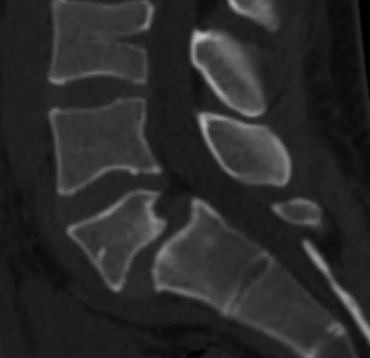

FRATURAS OSTEOPORÓTICAS

O envelhecimento da população é notado nos consultórios, com o aumento de doenças relacionadas à senilidade. As fraturas osteoporóticas causam dor, encurtamento do tronco e mudanças no alinhamento da coluna. Pacientes com osteoporose podem ter fraturas mesmo sem acidentes.

ESPONDILOLISTESE

O escorregamento de uma vértebra sobre a outra pode ser de causa congênita ou adquirida, pode causar dor na coluna ou sintomas irradiados para os membros. Podem afetar pessoas jovens, em fase de crescimento, adultos que tiveram espondilolistese na infância e não descobriram, ou idosos que começam a ter o escorregamento da vértebra por motivos degenerativos.

ESTENOSE DE CANAL VERTEBRAL

O estreitamento do canal vertebral, por onde passa a medula e os nervos espinais, é comumente causado por alterações do envelhecimento das articulações. Os sintomas de compressão de medula e nervos são dor e perda de funções neurológicas, tais como força, sensibilidade, equilíbrio na marcha e resistência física nos membros inferiores.

CIRURGIA DE ARTRODESE PARA DOENÇAS DEGENERATIVAS

A fixação das vértebras pode ser feita em qualquer segmento da coluna – cervical, torácica ou lombar. As cirurgias podem ser feitas pela frente, pela lateral ou por trás, ou então, por vias combinadas.